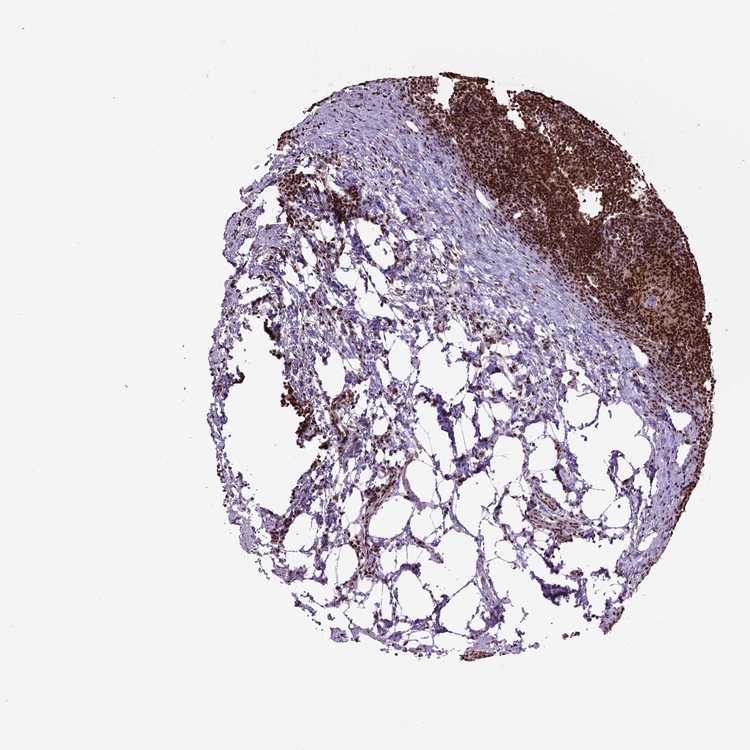

TISSUE PRIMARY DATA LYMPH NODE Show tissue menu

Lymph node

LYMPH NODE - Expression summary

LYMPH NODE - Antibody stainingi

Antibody staining in the annotated cell types in the current human tissue is reported as not detected, low, medium, or high, based on conventional immunohistochemistry profiling in selected tissues. This score is based on the combination of the staining intensity and fraction of stained cells.

Each image is clickable and will lead to virtual microscopy that enables deeper exploration of all samples and also displays staining intensity scores, fraction scores and subcellular localization as well as patient and tissue information for each sample.

Antibody CAB016114Antibody CAB069989

Germinal center cells HighHigh

Non-germinal center cells HighHigh